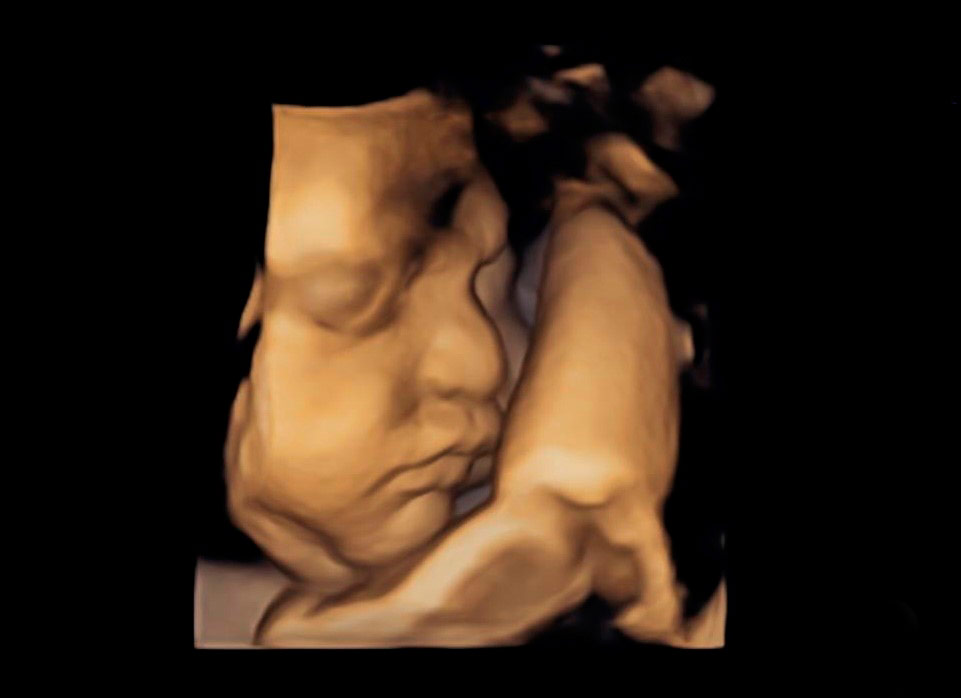

Un ultrasonido temprano puede confirmar un embarazo normal, determinar la edad del embrión, detectar un embarazo ectópico o posible amenaza de aborto, determinar la frecuencia cardíaca del embrión, detectar embarazos múltiples, identificar problemas de la placenta, el útero, trompas y los ovarios. A lo largo del embarazo es un complemento en la consulta necesario para determinar una adecuada evolución.